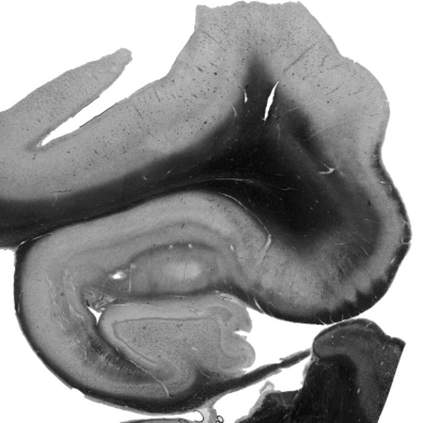

Understanding the cortical organization of the human brain requires interpretable descriptors for distinct structural and functional imaging data. 3D polarized light imaging (3D-PLI) is an imaging modality for visualizing fiber architecture in postmortem brains with high resolution that also captures the presence of cell bodies, for example, to identify hippocampal subfields. The rich texture in 3D-PLI images, however, makes this modality particularly difficult to analyze and best practices for characterizing architectonic patterns still need to be established. In this work, we demonstrate a novel method to analyze the regional organization of the human hippocampus in 3D-PLI by combining recent advances in unfolding methods with deep texture features obtained using a self-supervised contrastive learning approach. We identify clusters in the representations that correspond well with classical descriptions of hippocampal subfields, lending validity to the developed methodology.